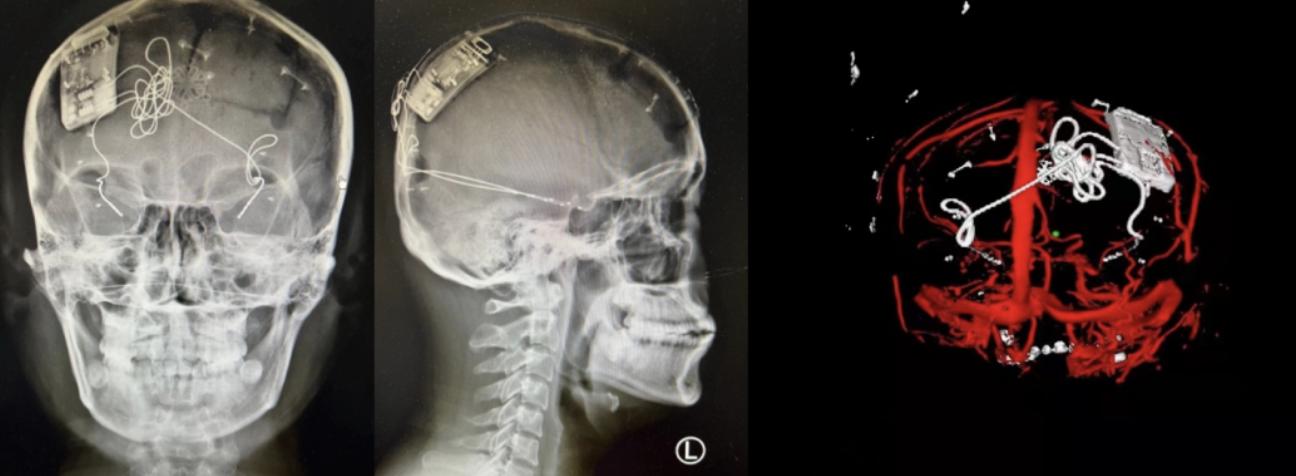

△患者影像评估

这次手术过程顺利,术中刺激器各项指标均工作正常,术后重建显示电极位置精准,脑电信号清晰。最终,Epilcure™国家药品监督管理局注册临床试验的首例患者。